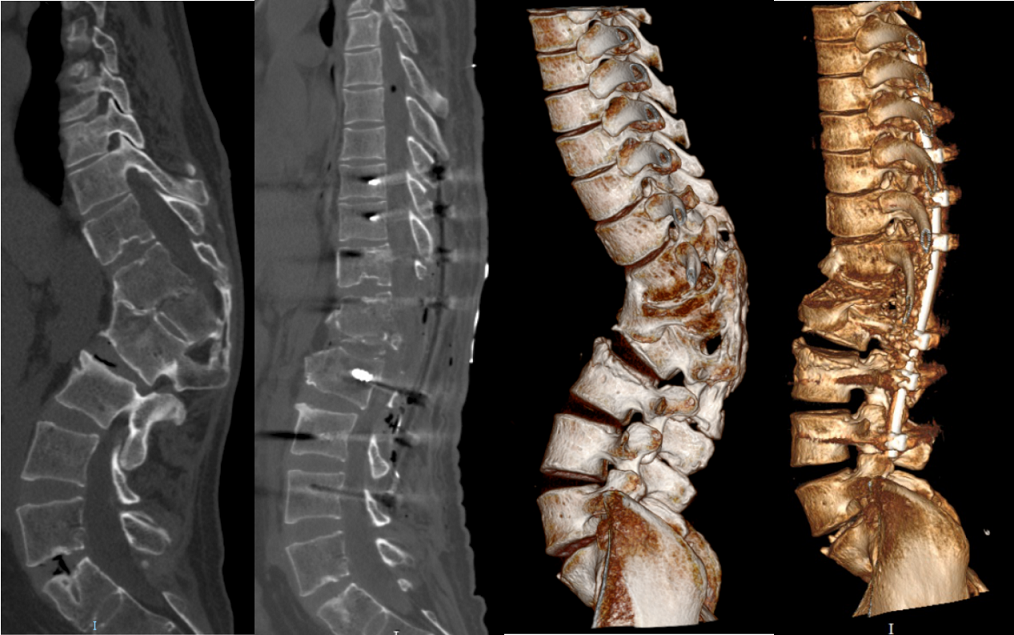

病例分享:脊柱后凸畸形矫形术

经椎弓根截骨治疗合并骨质疏松的重度脊柱后凸